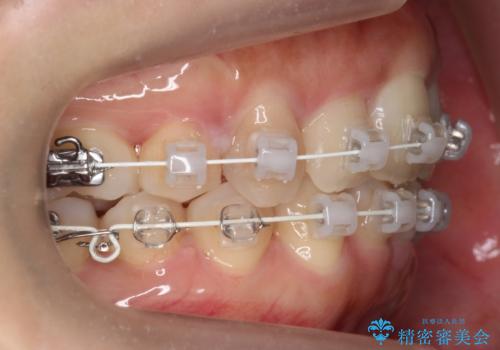

- 矯正装置

- ワイヤー矯正

- 2年4ヶ月

- 10-30回